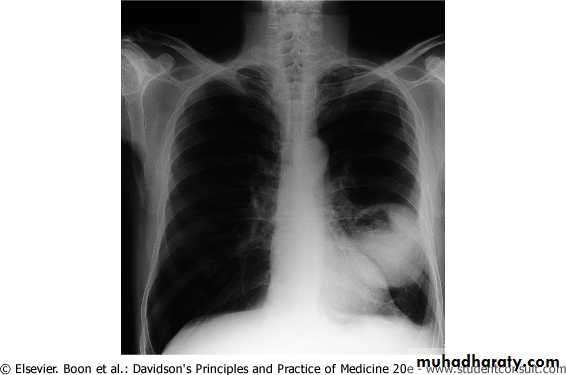

Chest radiography shows multiple pulmonary nodules of varying sizes consistent with metastatic cancer.

Chest CT scan shows multiple round nodules and masses of varying sizes in both lungs, consistent with metastases. There are also small bilateral pleural effusions.

Multiple and bilateral secondaries

Computed tomography scan showing nodular thickening of interlobular septa (white arrow), seen as polygonal arcades with thickened and nodular limbs, and ground-glass opacities (black arrows).

Chest radiography of a 31-year-old woman showing diffuse interstitial and septal thickening (arrow) in both lungs.

Lymphangitic carcinomatosis